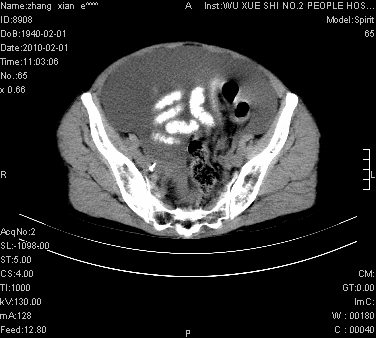

标题: CT24434:70岁 女 腹胀,腹水原因待查 [打印本页]

标题: CT24434:70岁 女 腹胀,腹水原因待查

大量腹水,脾脏囊性占位,子宫颈占位,右侧腹股沟淋巴结肿大,建议+c,先查妇科。

腹盆腔大量积液,子宫增大,子宫颈增大外形不规则,内见低密度影,膀胱后壁显示不清,右腹股沟肿大淋巴结,脾脏囊性占位,子宫颈占位,子宫颈癌?建议增强。

腹盆腔大量积液,子宫增大,子宫颈增大外形不规则,内见低密度影,膀胱后壁显示不清,右腹股沟肿大淋巴结,脾脏囊性占位,子宫颈占位,子宫颈癌?建议增强。支持!